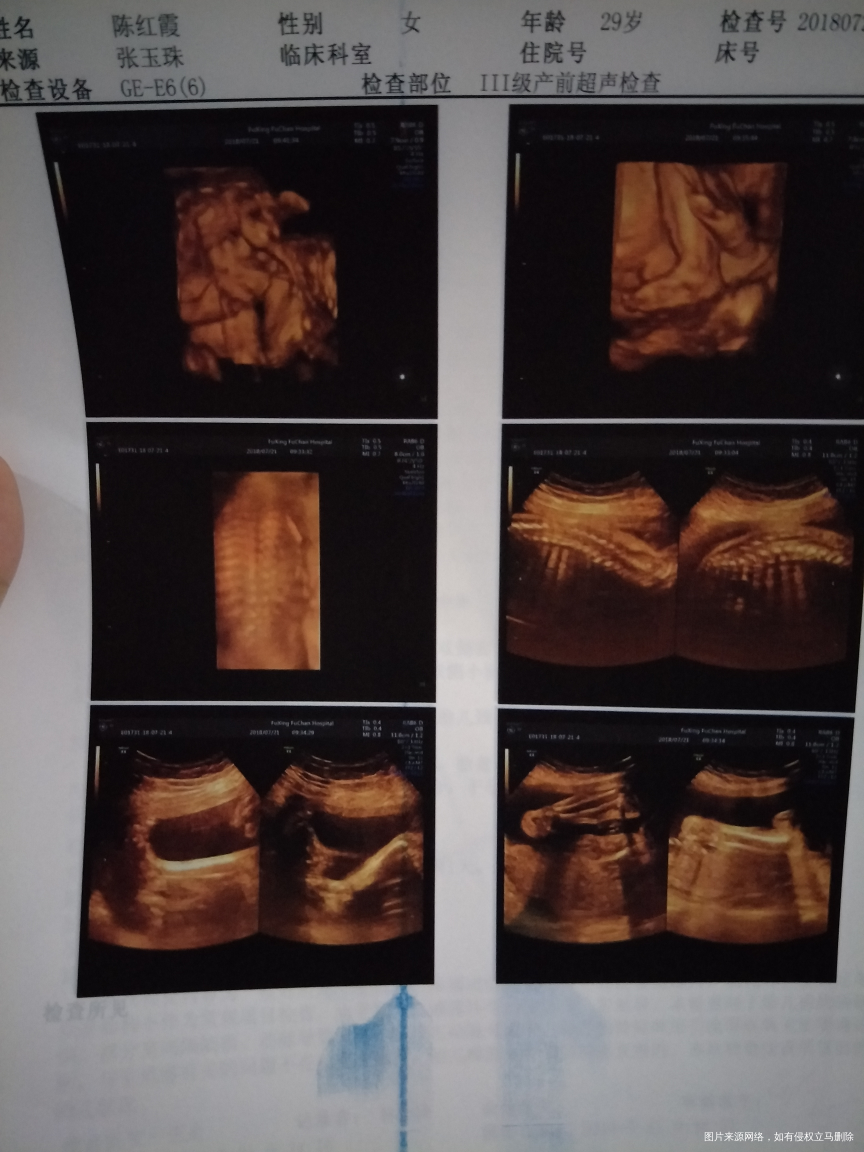

怀孕26+6,做的四维彩超,看不见宝宝的手指头和脚指头,正常吗?好担心啊,麻烦医生帮忙看看,

你好,宝妈。宝宝总体发育均正常,至于手指脚趾不清楚,多半宝宝体位有关。之后可以再次复查,定期产检,祝你好孕。如果我的建议对您有帮助,请记得选择点击采纳哦。

补充说明:宝妈可以了解彩超最下面几行的说明,手脚,耳等等不是彩超检查的项目,因为毕竟宝宝在子宫内,除非MRI或是更高超的检查才能看见“细枝末节”。目前已经接近孕晚期,注意宝宝胎动,定期产检,祝你好孕。如果我的建议对您有帮助,请记得选择点击采纳哦。